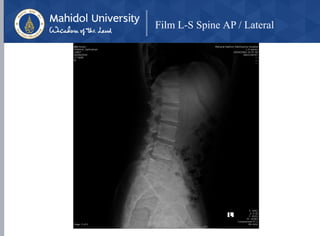

Film L-S Spine AP / Lateral

• X-Ray : L-S spine AP, lateral

• loss of lordosis (spasm)

• loss of disc height

• lumbar spondylosis